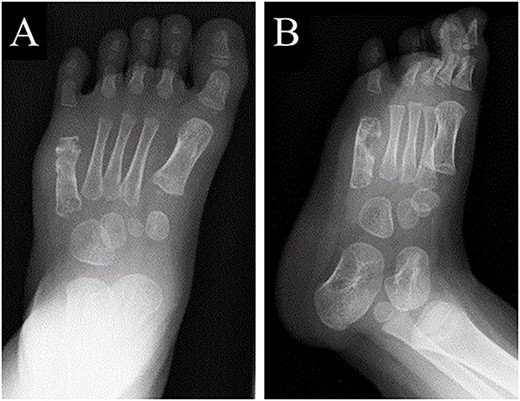

A 21-month-old Japanese female infant presented with a swollen mass on the dorsolateral aspect of the left foot. Her parents noticed the mass and brought the patient to our hospital. The patient had no past medical histories or complications prior to the occurrence. In addition, she received the BCG vaccine at the age of 4 months in Japan. At first visit to our hospital, physical examination revealed the ~3 × 3 cm mass was located on the dorsolateral aspect of the left foot and was hard accompanied by local heat (Fig. 1). Plain radiographs of the left foot showed a lytic lesion without periosteal reaction in the fifth metatarsal bone (Fig. 2). Magnetic resonance imaging (MRI) showed an isointense lesion on T1-weighted images and a hyperintense lesion on T2-weighted images around and within fifth metatarsal (Fig. 3). Gallium scintigraphy revealed intense uptake in the patient’s left foot (Fig. 4). In addition, laboratory examination was within normal. Based on medical history, clinical and imaging findings, we considered the possibility of neoplasia or osteomyelitis and performed an open debridement and biopsy of the lesion to make a diagnosis. The lesion was yellow and consisted of weak, adipose-like tissue that surrounded and continued into the inferior of the fifth metatarsal bone (Fig. 5). The lesion inside and outside the bone was resected as much as possible. Histopathologic examination of the lesion showed granulomatous inflammation including anaplastic giant cells, Langerhans-type giant cells and caseous necrosis (Fig. 6). Based on these results, TB or BCG osteomyelitis was considered as a diagnosis. The tuberculin test was positive, but the QuantiFERON TB test was negative. In addition, samples analyzed using polymerase chain reaction did not identify M. tuberculosis, but did identify the BCG Tokyo-172 strain. Per these findings, the patient was diagnosed with BCG osteomyelitis of the fifth metatarsal and oral treatment with anti-TB medicine including isoniazid (100 mg/day) and rifampicin (150 mg/day) was started. Clinical findings included reduction in swelling of the mass and gradual remodeling of the lytic lesion of the fifth metatarsal on plain radiographs (Fig. 7). However, 10 months after starting the anti-TB treatment, the mass recurred, and MRI revealed a residual high-intensity lesion around and inside the fifth metatarsal on T2-weighted fat-suppressed images (Fig. 8). It was determined that the lesion was difficult to control with anti-TB treatment alone, so an open debridement for the lesion was performed again. Histopathologic examination of the lesion revealed an epithelioid granuloma with necrosis. Therefore, the anti-TB treatment was continued. Six months after the second surgery, clinical and radiographic image findings showed complete improvement (Fig. 9). As a result, anti-TB treatment was ended. At the time of writing this report, 8 years after starting anti-TB treatment, there has been no recurrence.

Plain radiographs of the left foot showing a lytic lesion without periosteal reaction in the fifth metatarsal bone in (A) anteroposterior and (B) oblique views.